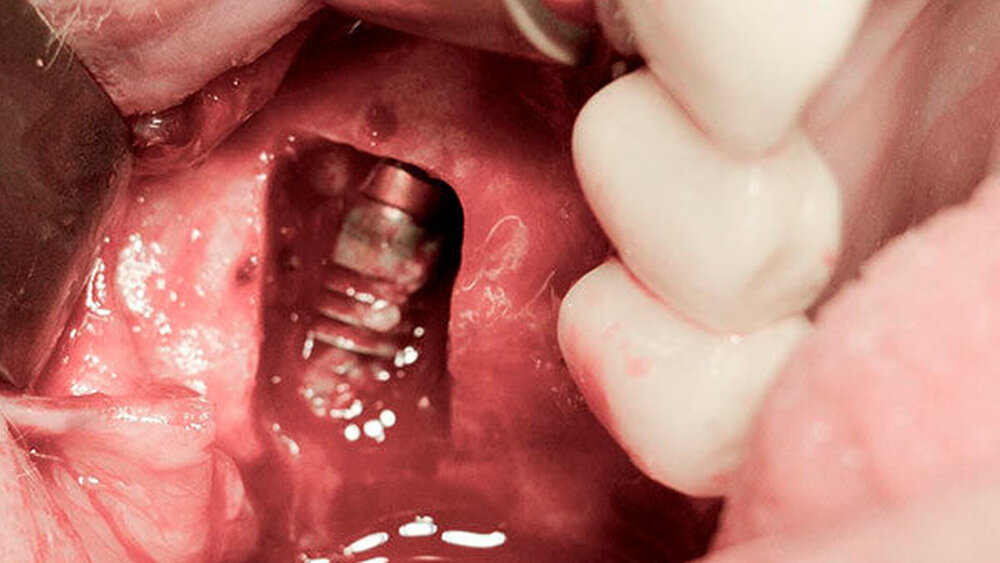

Nach Freilegung und prothetischer Versorgung im August 2015 waren die Titanimplantate und der dazwischen befindliche Zahn 15 zwei Jahre lang beschwerdefrei in situ – bis Ende April 2017 der Zahn 15 beim Kauen eines Fleischstücks spontan in die Kieferhöhle luxierte (Abbildungen 1 und 2).

Eine Sinusitis maxillaris bestand nicht und die Patientin litt unter keinerlei Schmerzen. Allein die unterbrochene Zahnreihe störte.